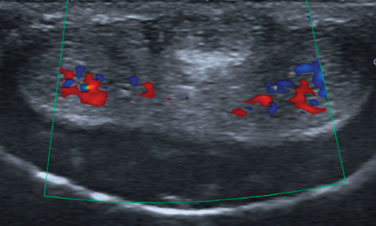

Eco Doppler

¿ Qué es la ecografía doppler de pene?. La ecografía doppler de pene es la técnica de primera línea ideal para…